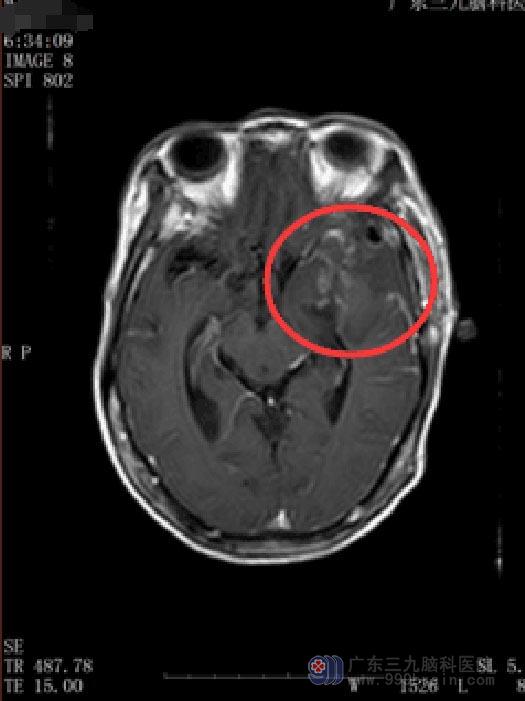

10天前开始出现阵发性头晕;两天因头晕摔倒致“右锁骨骨折”。当地医院检查示肿瘤较前增大,广东三九脑科医院MR显示:1.左侧鞍旁占位性病变,大小约4.5cm×3.9cm×4.5cm,考虑神经鞘瘤可能,待排骨源性肿瘤。

由于占位巨大,通过传统的单一开颅或经鼻蝶入路手术不可能全切肿瘤,若是采取分期手术,则将会大大增加患者再次手术风险以及住院费用。经过充分的术前讨论、评估后,鲁明副院长决定为其实施“内镜经鼻蝶+左侧翼点联合入路颞下窝巨大占位切除术”。导航定位,确定肿瘤位置,显微镜下分块全切肿瘤,术中视神经、动眼神经、颈内动脉及其分支血管保护完好,术后患者恢复良好,视力、视野较前好转,无脑脊液漏发生,无尿崩及电解质紊乱。术后病理:(左侧鞍旁)神经鞘瘤。